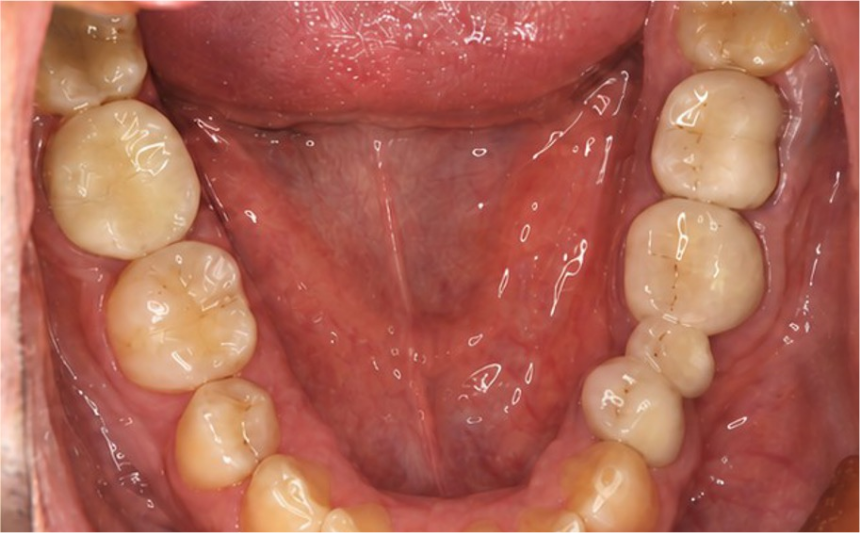

BEFORE

銀歯が目立つ

銀歯が目立つ

再むし歯も発見

再むし歯も発見

清潔感と長持ちを重視して相談

AFTER

自然で白い奥歯に

自然で白い奥歯に

噛み合わせも改善

噛み合わせも改善

人前で口を開けるストレスが減ったとのこと

人前で口を開けるストレスが減ったとのこと

| 治療内容 | ジルコニアクラウンで再修復 むし歯を徹底除去し、適合精度の高い治療へ。 |

|---|---|

| 治療期間 | 約2〜3週間 |

| 費用 | 88,000円〜132,000円(税込) |